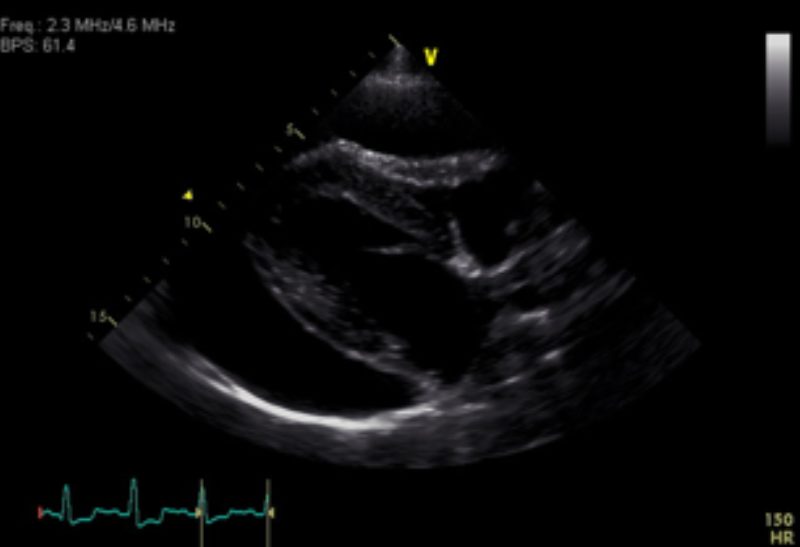

Die Besitzerin berichtete, dass „Timmi“ beim Einladen in das Auto kurz zusammengebrochen sei und sich sein Zustand bei der Anfahrt noch weiter verschlechtert hätte. In der Untersuchung war der Hund sehr matt und atmete verstärkt (Bild 1). Neben blassen Schleimhäuten und einem schwachen Puls war vor allem eine deutlich erhöhte Herzfrequenz bei eher leisen Herztönen auffällig. Eine Röntgenaufnahme des Brustkorbes zeigte eine deutlich vergrößerte und abgerundete Herzsilhouette und führte zu dem Verdacht eines Herzbeutelergusses (Bild 2). Zur weiteren Abklärung wurde ein Herzultraschall durchgeführt, womit die Verdachtsdiagnose schnell bestätigt werden konnte (Bild 3).

Aufgrund der lebensbedrohlichen Situation ist umgehendes Handeln erforderlich. „Timmi“ erhielt zunächst zur Stabilisierung des Kreislaufes Flüssigkeit über einen Venenzugang. Anschließend wurde der Bereich der Punktionsstelle rasiert, desinfiziert und örtlich betäubt. Die Flüssigkeit im Herzbeutel wurde mit einer Kanüle, die über einen Schlauch mit einer großen Spritze verbunden ist, abgezogen. Bei „Timmi“ ließen sich 310 ml rötliche Flüssigkeit entfernen (Bild 4). Nach der Punktion konnte man im Ultraschall bereits erkennen, dass das Herz - insbesondere jedoch der rechte Vorhof - wieder gut gefüllt war und sich besser kontrahierte (Bild 5). Die Laboruntersuchung des Flüssigkeitspunktats ergab ein blutiges Zellbild. „Timmi“ war direkt nach Abpunktion der Flüssigkeit wieder deutlich agiler und nahm bereits Futter auf. In Absprache mit den Besitzern entschieden wir uns, ihn für weitere Untersuchungen und zur Kontrolle der Ergussmenge am Folgetag für eine Nacht stationär aufzunehmen.